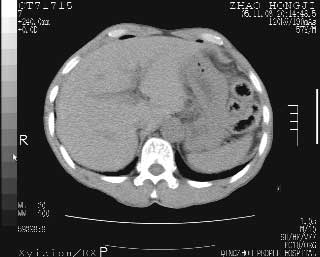

临床资料:男性,57岁,上腹部疼痛并5天,突然加重并延及全腹伴恶心5小时入院。胰淀粉酶化验在正常范围。检查:腹肌紧张,全腹压痛、反跳痛,尤以右上腹部为著。肠鸣音减低。血常规:wbc14.6x10/9, n:11.3x10/9 ,血压:135/90mmhg. 胸部透视:腹部肠腔轻度张气,未见其它异常改变。

肝缘见少许气体,胰尾部见少许气体包饶(蓝色圈),12指肠上部或球部邻近胆囊周边也可见少许气体影(黄色圈),并忖托出胆囊壁,12指肠远段肠道内未见明显气体(白色箭)。

肝脏前缘见少量积气、胰尾部见少许气体包饶,肾前筋膜未见增厚,临床淀粉酶不高,意见:上消化道穿孔。

入院3小时后行剖腹探查术,见腹腔内大量脓性混浊液约1000ml,十二指肠球部溃疡穿孔,溃疡面约2.5x2cm,穿孔直径约0.6cm。胃内容物外益,周围组织炎性水肿明显。行十二指肠穿孔修补术。术后诊断:

1、十二指肠溃疡穿孔

2、弥漫性腹膜炎

对于少量的腹腔游离气体,ct检查较普通透视有绝对的优势,它不仅可以看到肝脏前上缘的气体,而且还能够看到小网膜区的游离气体。从而可以肯定诊断。各位分析战友的很好,感谢大家的参入!